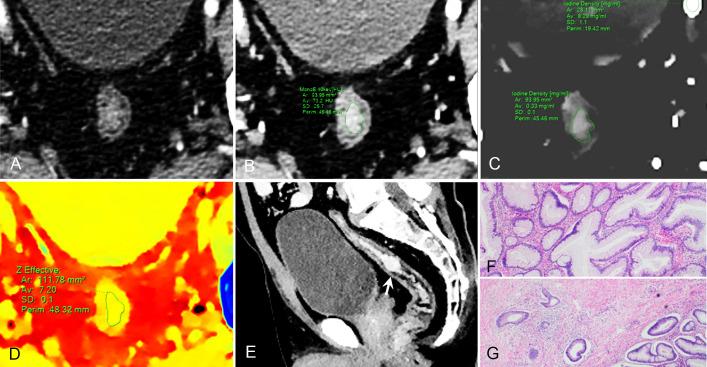

METHODS

A total of 131 patients (mean 62.7 ± 12.9 years; 72 female, 59 male) with pathologically confirmed CRAC (35 pT1-2, 61 pT3, and 35 pT4; 32 high grade and 99 low grade), who received dual-phase DLCT were enrolled in this retrospective study. Normalized iodine concentration (NIC), slope of the spectral HU curve (λHU), and effective atomic number (Eff-Z) were measured for each lesion by two radiologists independently. Intraobserver reliability and interobserver agreement were assessed. The above values were compared between three pT-stage and two histologic-grade groups. The correlation between the pT stages and above values were assessed. Receiver operating characteristic (ROC) curves were calculated to evaluate the diagnostic efficacy.

Intra-class correlation coefficients were ranged from 0.856 to 0.983 for all measurements. Eff-Z [7.21(0.09) vs 7.31 (0.10) vs 7.35 (0.19)], NIC [0.11 (0.05) vs 0.15 (0.08) vs 0.15 (0.08)], NIC [0.27 (0.06) vs 0.34 (0.11) vs 0.35 (0.12)], λHU [1.20 (0.45) vs 1.93 (1.18) vs 2.37 (0.91)], and λHU [2.07 (0.68) vs 2.35 (0.62) vs 3.09 (1.07)] were significantly different among pT stage groups (all <0.001) and exhibited a positive correlation with pT stages (= 0.503, 0.455, 0.394, 0.512, 0.376, respectively, all <0.001). Eff-Z [7.37 (0.10) vs 7.28 (0.08)], NIC[0.20 (0.10) vs 0.13 (0.08)], NIC[0.35 (0.07) vs 0.31 (0.11)], and λHU [2.59 (1.11) vs 1.63 (0.75)] in the high-grade group were markedly higher than those in the low-grade group (all <0.05). For discriminating the advanced- from early-stage CARC, the AUCs of Eff-Z, NIC, NIC, λHU, and λHU were 0.83, 0.80, 0.79, 0.86, and 0.68, respectively (all <0.001). For discriminating the high- from low-grade CARC, the AUCs of Eff-Z, NIC, NIC, and λHU were 0.81, 0.81, 0.64, and 0.81, respectively (all <0.05).